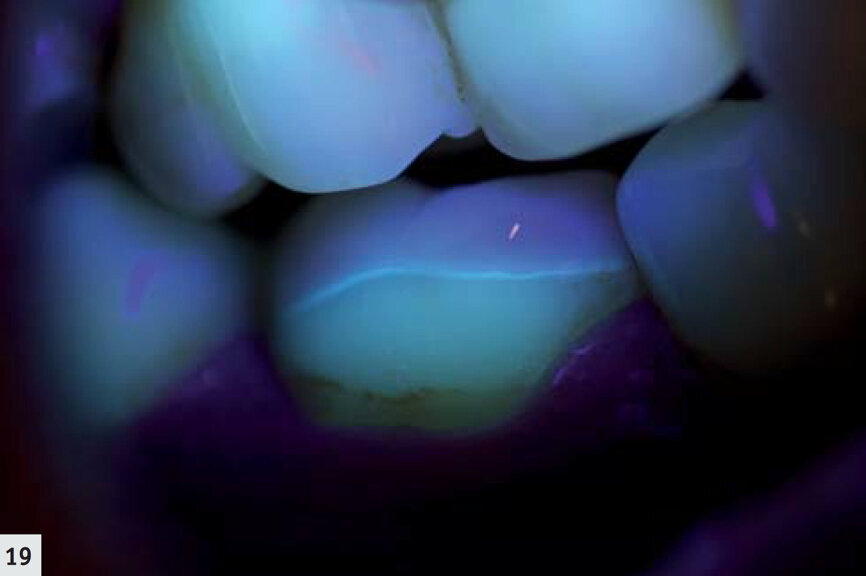

Fig. 19 : Même dent que sur la Fig. 18. La fine ligne du scellement (G-ænial Antérior, teinte A2) est visible grâce à l’utilisation de D-Light Pro en mode détection. Les limites marginales présentent une excellente adaptation et sont exemptes de caries.

La majorité des résines composites émettent une hyperfluorescence sous le rayonnement proche-UV.6, 7 Les autres restaurations, minimes, peuvent facilement être observées en mode détection (Fig. 14). De cette façon, il est possible de déceler la présence d’un surplomb et de définir plus aisément les espaces marginaux (Fig. 15). L’élimination des restaurations défectueuses devient ainsi beaucoup plus facile et s’effectue sans retrait inutile de tissu dentaire sain. De plus, ce mode représente un outil très utile au cours des techniques de scellement ; les excès de ciment résine sont immédiatement détectés et peuvent donc être éliminés (Fig. 16) sans polymérisation simultanée ; après le nettoyage, le même dispositif peut être utilisé pour polymériser les limites marginales (Fig. 17). Au cours du suivi, les restaurations sont mieux visualisées (Figs. 18–19) et il est possible d’examiner rapidement et complètement leurs limites marginales.